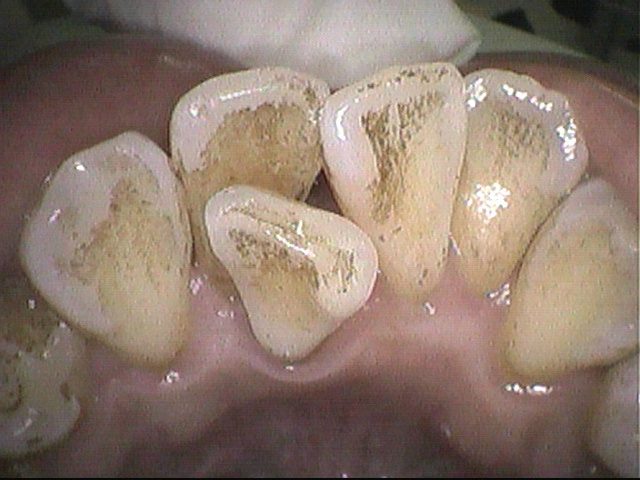

クリーニング前(3ヶ月後)

クリーニング後

普段は紅茶をよく飲まれているそうです。

紅茶は着色を起こしやすく、他にステインがつきやすい飲み物としては

赤ワイン、コーヒー、抹茶、緑茶、ココアなどがあります。

ステインをできる範囲で除去し、きれいになりました。